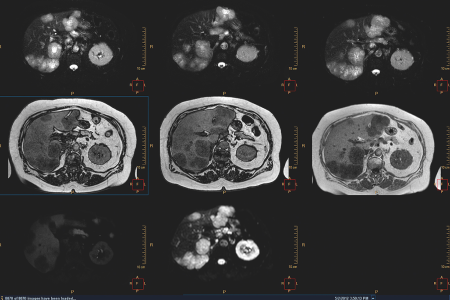

Strumenti di visualizzazione avanzata oncologica che valutano lo stadio e la risposta al trattamento

La cura del cancro si sta orientando verso scelte di trattamento ottimali e personalizzate, adattate in base alle esigenze dei singoli pazienti. Tutte le informazioni relative alla diagnostica e alla genomica del cancro vengono integrate per consentire agli specialisti del cancro di prendere decisioni informate durante la fase diagnostica. La digitalizzazione dell'assistenza sanitaria consente di rendere disponibili in formato digitale tutti i dati diagnostici, ad esempio i test radiologici, patologici e diagnostici in vitro.

In Philips, consentiamo la caratterizzazione e la stadiazione della malattia di un paziente in modo sicuro riducendo il rischio di errori nella categorizzazione della stadiazione.